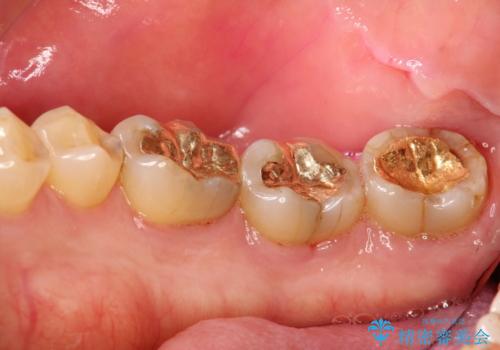

- 2カ月ごとにメンテナンスにいらしている方です。染め出しをしての歯磨きチェックとPMTC30分コースを行いました。

染め出し液を使ってプラークを染め出すことにより、普段の歯みがきで磨き残している場所を目で確かめることができます。

日々の歯磨きを上達するには、まずどこが磨けていないか認識することが大切です。